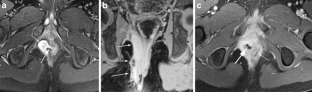

Perianal disease in pediatric Crohn disease: a review of MRI findings

Perianal complications of Crohn disease are a common occurrence in children and can result in significant morbidity when not accurately characterized prior to surgical intervention. MRI is an excellent imaging modality for the evaluation of perianal inflammatory bowel disease – allowing characterization and detailed description of perianal fistulas. MRI has many advantages over other imaging modalities for the pediatric patient. Radiologists will benefit from a sophisticated understanding of perianal anatomy, the classification of perianal fistulas, the advantages MRI offers in characterization of perianal fistulas as well as the common and incidental findings that are important in the MRI evaluation of perianal inflammatory bowel disease in children. Perianal fistulas are found at a high rate in pediatric referrals and are more commonly found in male patients.